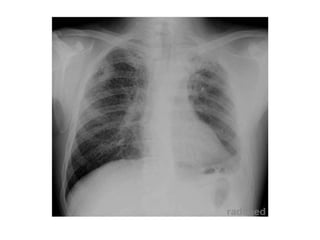

NEUMONIA ATIPICA (legionella)

NEUMONIA ATIPICA (M. Pneumonae)

NEUMONIA ATIPICA (C. Pneumonae)